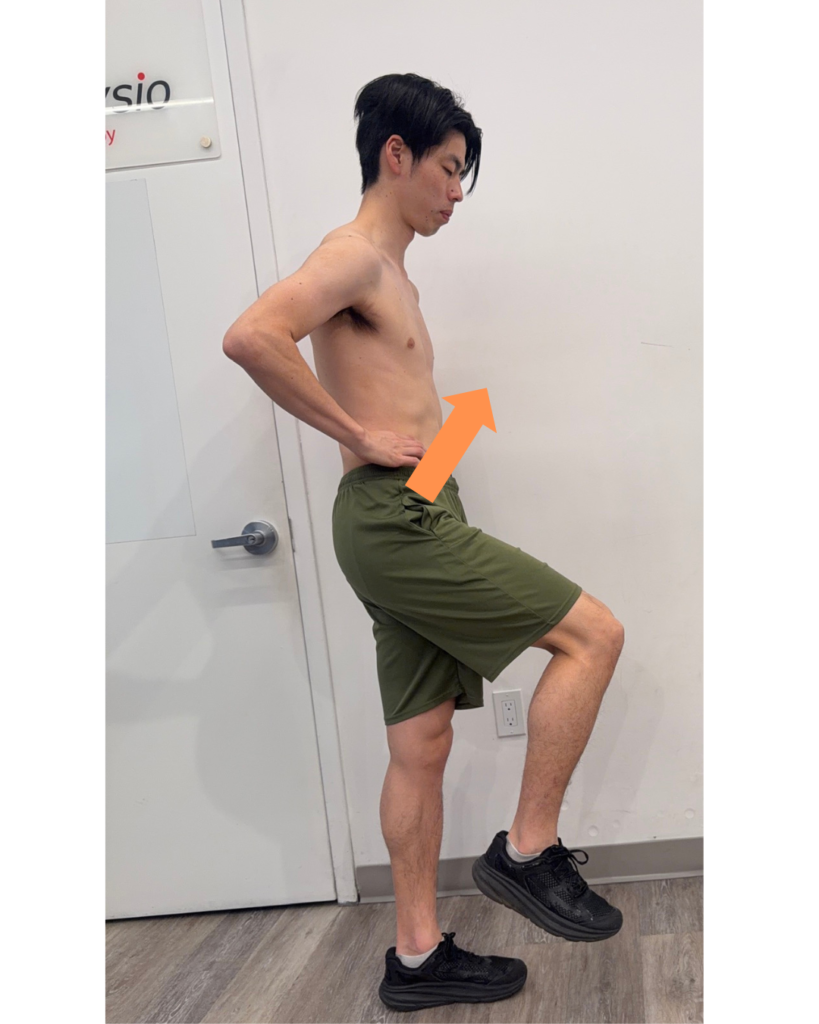

1. Anterior Elevation (Swing Phase)

Anterior elevation occurs when the pelvis moves forward and upward on the side of the swinging leg.

Role:

- Initiates limb advancement

- Assists with foot clearance

- Contributes to forward momentum

Muscular connection: abdominal muscles and hip flexors

1. Anterior Elevation Exercise: High Stepping

Goal: Improve pelvic lift and forward drive during swing phase

How to perform:

- Stand tall

- Lift one knee toward your chest in a marching motion

- Focus on initiating the movement from the pelvis

- Alternate sides with control

- Be aware of stand leg posterior depression

Goal:

- Improve foot clearance

- Reduce compensations like trunk leaning